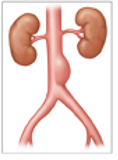

A 67-year-old man presents to his primary care physician due to vague epigastric discomfort.

He denies it being associated with meals and reports that this pain occurred insidiously.

Medical history is significant for hypertension.

He has been smoking 1-pack of cigarettes per day for the past 30 years.

On physical exam, he has a pulsatile abdominal mass that is tender to palpation.

An abdominal ultrasound is performed, which demonstrates a 6 cm abdominal aortic aneurysm.

He is scheduled for an elective abdominal repair surgery for the following day.

Aortic aneurysm and dissection

May be incidental on rad scans

Palpable, pulsatile abdominal mass

May be palpable as a pulsatile mass (AAA)

Bruit may be heard from turbulent blood flow (AAA)

Abdominal pain

Hypotension

Pulsatile abdominal mass

Ruptured or leaking AAA “triad” Aortic Aneurysm

Pulsatile mass Aortic Aneurysm